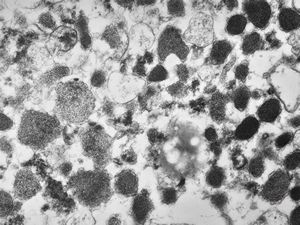

M, 49y. | pancreatic tumor (insulinoma v.s.)